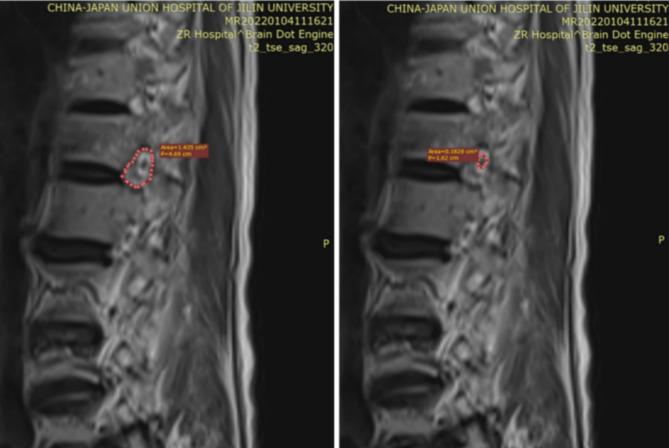

This study included a total of 104 patients based on the presence or absence of intercostal neuralgia.The results of multifactorial logistic regression analysis showed that injured vertebral intervertebral foraminal area (P = 0.0008, regression coefficient estimate 0.0490, 95% confidence interval 0.0219-0.0798, OR = 1.0503), injured vertebral intervertebral foraminal volume (P = 0.0001, regression coefficient value - 0.0028, 95% confidence interval - 0.0044 to -0.0015, OR = 0.9972), and nerve root area (P = 0.0038, regression coefficient estimate=-0.0876, 95% confidence interval - 0.1506 to -0.0309, OR = 0.9161) were independent associated factors.The fatty degeneration ratio have a positive promotional effect on the probability of developing intercostal pain.The area under the ROC curve (AUC) of the prediction model was 0.851, which indicated that the line graph model had a certain degree of predictive validity.

根据是否存在肋间神经痛,本研究共纳入104例患者。多因素logistic回归分析结果显示,损伤椎体椎间孔面积(P = 0.0008,回归系数估计值0.0490,95%置信区间0.0219 - 0.0798,OR = 1.0503)、损伤椎体椎间孔体积(P = 0.0001,回归系数值 - 0.0028,95%置信区间 - 0.0044至 - 0.0015,OR = 0.9972)和神经根面积(P = 0.0038,回归系数估计值 = - 0.0876,95%置信区间 - 0.1506至 - 0.0309,OR = 0.9161)是独立相关因素。脂肪变性率对发生肋间神经痛的概率有正向促进作用。预测模型的受试者工作特征曲线(ROC)下面积(AUC)为0.851,表明线性图模型具有一定程度的预测效度。